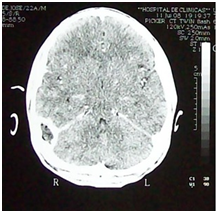

For this we used cadaveric dissection of adults preserved in Montevideo Solution (4% formaldehyde solution). The cranial vault was removed with Stryker saw and the posterior fossa was discovered resecting the posterior sector of the occipital bone to the foramen magnum (Figure 1). The mastoid is then drilled to reveal the lateral sinus (Figure 2).

Figure 1 Cadaveric dissection. Posterior view of the head without the cranial vault showing dura mater in supra and infra tentorial floors and the origin of the lateral sinuses at the level of the confluence sinnum (Prensa de Herofilo).

We can divide the intra-cranial venous drainage in three components, the deep veins, the superficial veins of the brain and the dural venous sinuses; these structures are exclusive to the encephalon. The whole system is designed so that the venous blood coming from the encephalon drains into the prensa de Herofilo (Confluence Sinnum) at the internal occipital protuberance in the posterior section of the cerebellar tentorium (Figure 1).

The sigmoid section of the lateral sinus is the terminus for the mastoid emissary vein, whose drainage area includes the mucoperiosteum of the mastoid cells and the mastoid region skin appendages (Figure 2). This explains the septic thrombosis of the lateral sinus due to septic thrombus in the emissary vein during infectious processes of the mastoid (Figure 3 & 4).2‒4

Figure 3 & 4 Right lateral sinus thrombosis in sigmoid section. Anatomic imaging correlation.